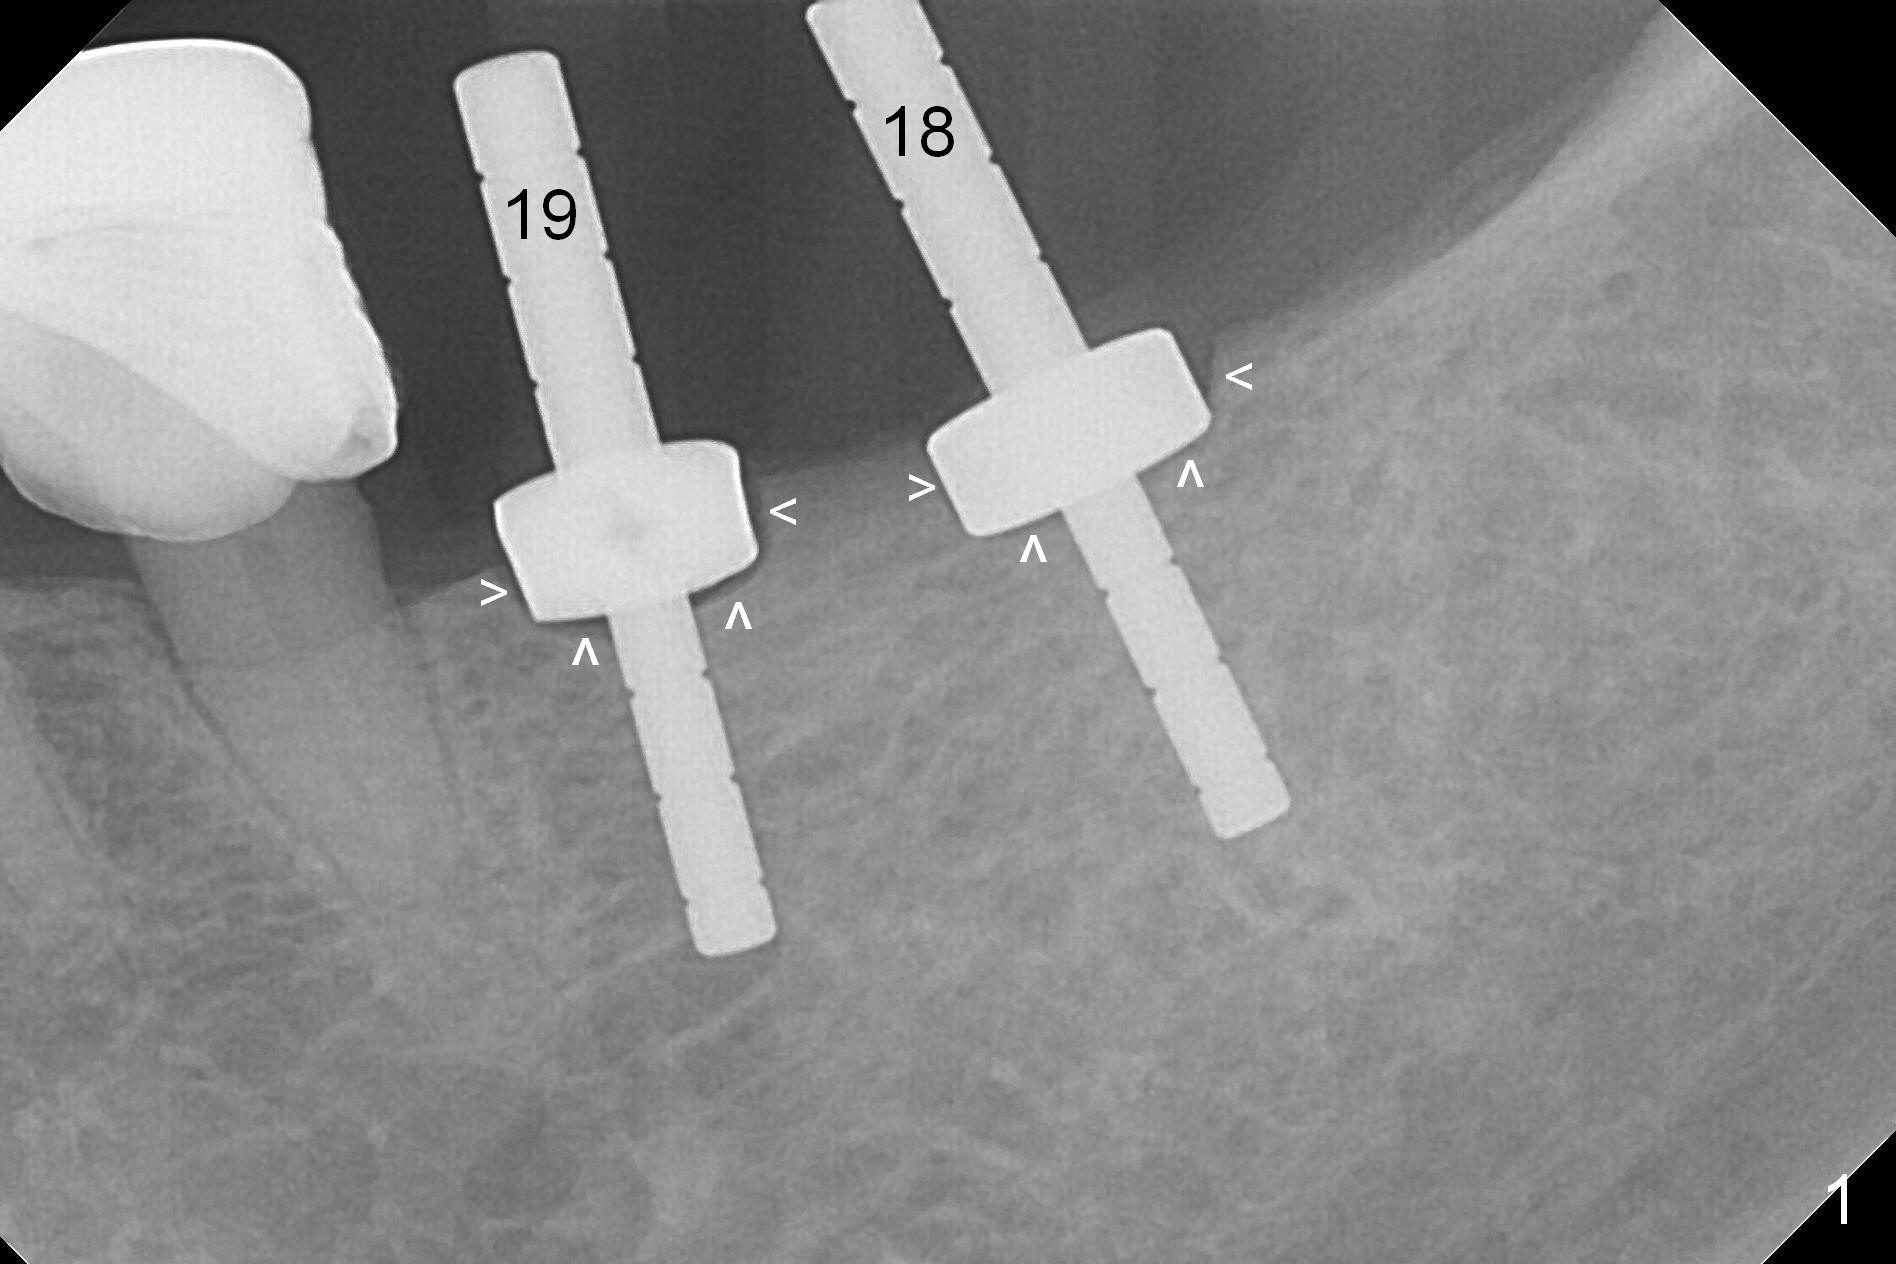

Because of the narrow ridge top at the sites of #19 and 18, it is reduced (Fig.1 arrowheads) prior to initial osteotomy with 1.6 mm pilot drill. After Magic Drills (3.3 and 4.3 mm at #19 and 18, respectively), 4x11 and 5x9 mm IBS implants are placed with insertion torque >35 Ncm with immediate placement of pair abutments (4.5x5.7(2) and 6.5x4(2) mm, Fig.2). In fact these sites are converted to a premolar and a 1st molar (because narrow ridge at #19). Following GBR and suturing, periodontal dressing is applied around the abutments for increased retention. The regional ridge reduction makes Marking Bur unnecessary (because of flat ridge top and the soft bone in this case) and more importantly there is no thread exposure upon implant placement. The trimmed site (concavity) is favorable for bone graft and membrane placement. One month postop, loose perio dressing is removed and replaced by a splinted nonfunctional provisional. The implant sites look normal nearly 3 months postop; there is no bone loss (Fig.3). Impression is taken. The crown/abutment at #18 is loose 3 years 2 months post cementation; when the crown/abutment is retightened, the abutment remains incompletely seated (Fig.4 <) in spite of reduction of the proximal contact (arrow). It may be due to the block of the distal crest (*). After use of 5.5 mm profile drill, the 6.5x4(2) mm abutment remains unseated (Fig.5). The smaller one (5x4(2) mm, Fig.6) is seated. When the redo crown is cemented, the surrounding gingiva is healthy with a short papilla between the implant crowns (Fig.7).